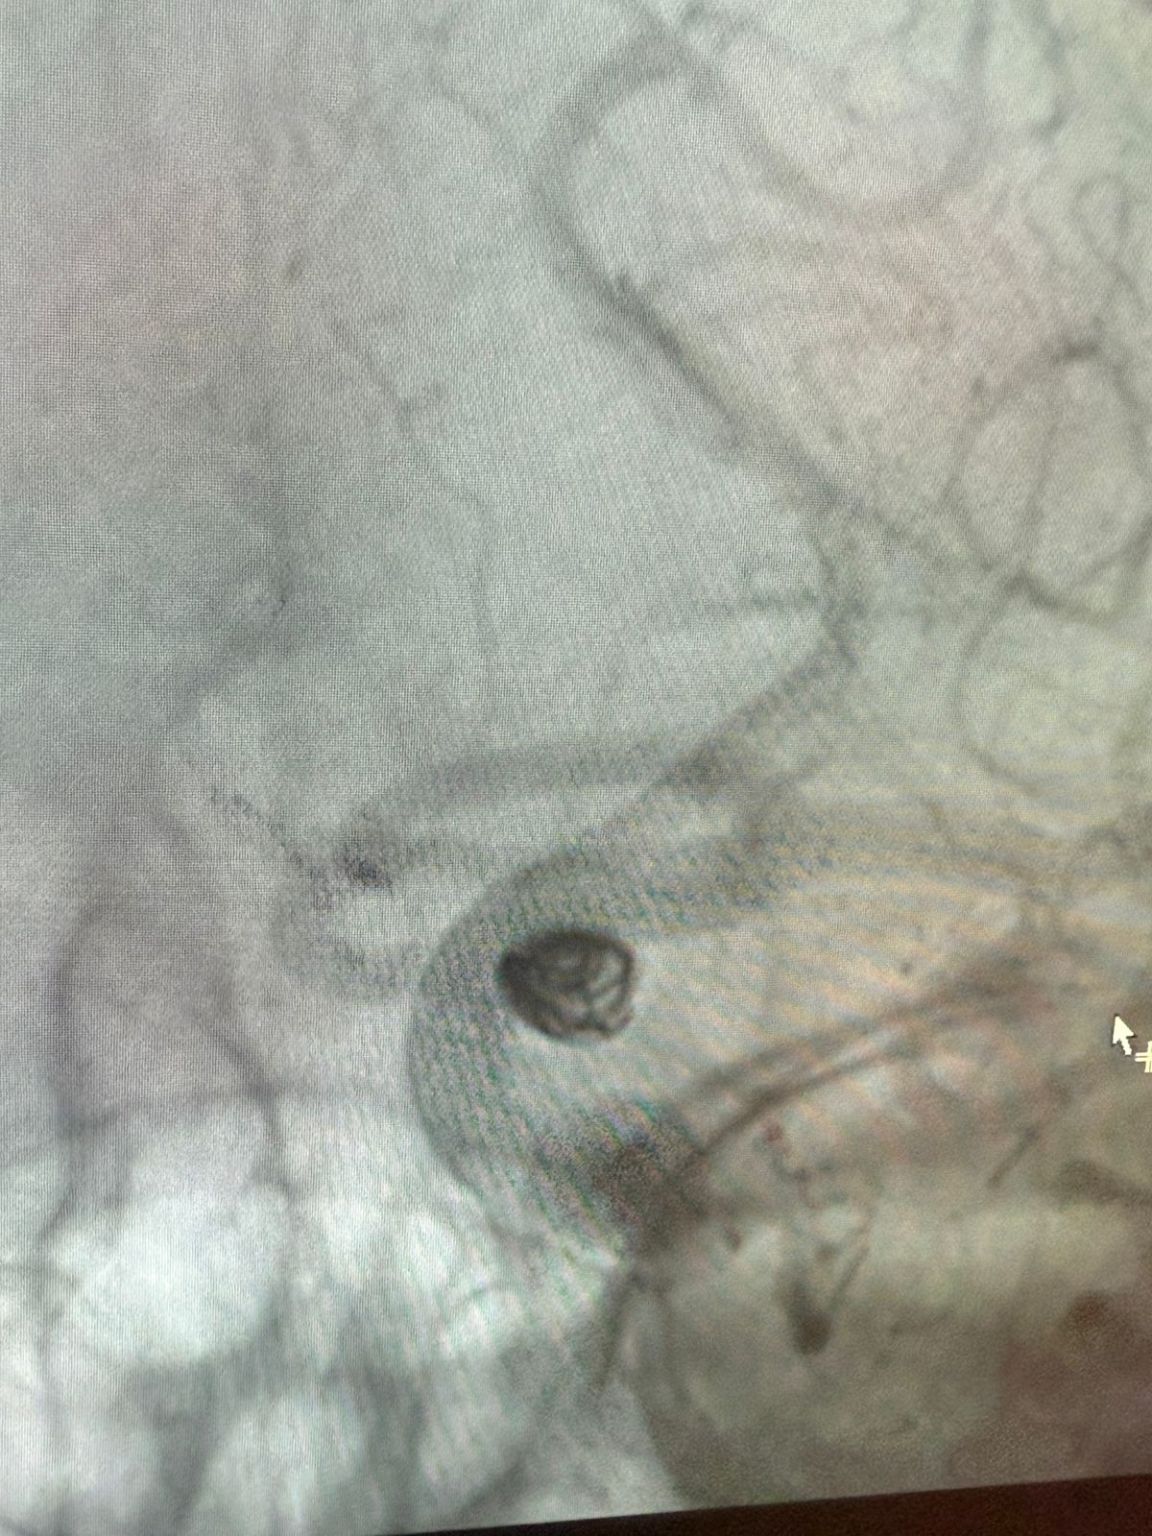

Nos complace compartir un procedimiento exitoso reciente en Clínica Alma Mater, Medellín, realizado por el Dr. Jorge Mutis.

El tratamiento utilizó el Nuva®Desvedor de flujo (TJED-D 5.0-14), Perdenser®Bobina 3D, y el paso de tierra®Microcatéter (TJMC18 Plus) para un aneurisma de arteria comunicante posterior.

Dr. Mutis destacó la excelente visibilidad del dispositivo y señaló que la recuperación fue suave. Expresó su gran satisfacción por el resultado final.